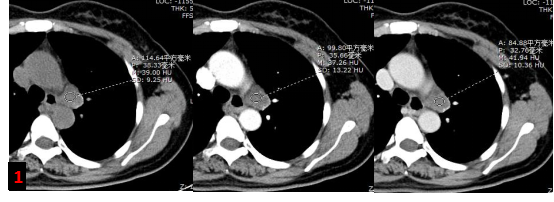

胸部強(qiáng)化CT?

主動脈弓左旁不規(guī)則混雜密度腫塊影,增強(qiáng)未見明顯強(qiáng)化,考慮腫大淋巴結(jié),轉(zhuǎn)移灶?(圖1)